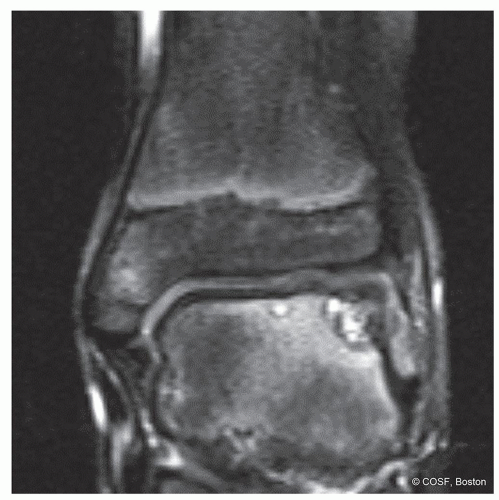

Hepple (1999) MRI Staging (T2)

Stage 1 Articular cartilage damage only

Stage 2a Cartilage injury, underlying fracture, edema

Stage 2b No edema

Stage 3 Detached with rim signal but nondisplaced

Stage 4 Displaced

Stage 5 Subchondral cysts (Figure 34.10)